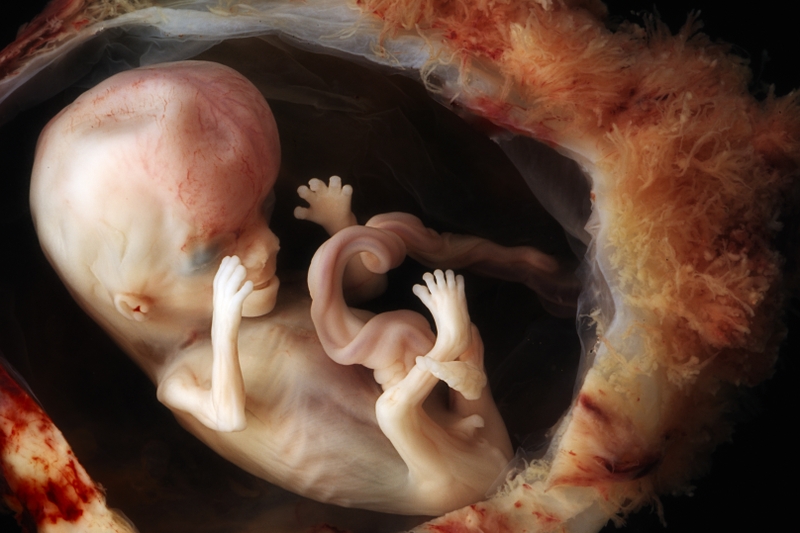

Khi bước sang tuần thứ 16, thai nhi đã có sự thay đổi đáng kể so với những tuần đầu tiên. Đây được xem là giai đoạn bản lề, khi các cơ quan quan trọng dần hoàn thiện và hoạt động nhịp nhàng hơn.

Ở tuổi thai này, bé thường dài khoảng 11 - 12 cm và nặng khoảng 100 gram. Xương bắt đầu cứng cáp hơn, khớp dần hình thành rõ rệt giúp bé có thể cử động tay chân linh hoạt. Các cơ mặt cũng bắt đầu phát triển, cho phép bé có những biểu cảm nhỏ như mím môi hoặc nhăn mặt.

Ở tuần 16, tai thai nhi bắt đầu phát triển và có thể bắt đầu phản ứng với âm thanh lớn, tuy nhiên khả năng nhận biết giọng nói của mẹ rõ ràng hơn sẽ xảy ra trong các tuần tiếp theo khi hệ thần kinh hoàn thiện hơn. Thính giác dần hoàn thiện và bé có thể di chuyển khi nghe thấy âm thanh quen thuộc. Ngoài ra, tóc, lông tơ, móng tay cũng bắt đầu xuất hiện, báo hiệu bé đang bước vào giai đoạn tăng trưởng nhanh chóng.

Siêu âm 3D/4D ở tuần 16 có thể giúp thấy khuôn mặt và các chuyển động của bé, nhưng hình ảnh chưa rõ nét như ở giai đoạn sau. Đặc biệt, hình ảnh nhịp tim đều đặn và mạnh mẽ là dấu hiệu cho thấy thai nhi đang phát triển khỏe mạnh.